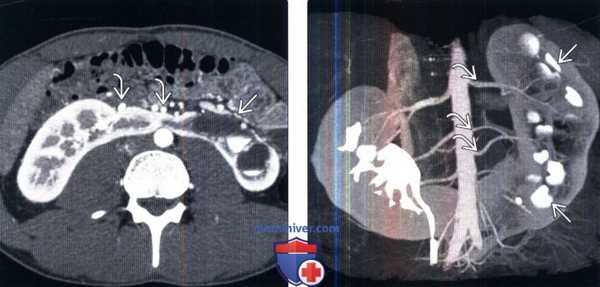

3. КТ при подковообразной почке:

• КТ с контрастированием:

о Позволяет определить структурные аномалии:

- Степень и локализация сращения: срединное или боковое сращение

- Степень мальротации почки

- Изменения почечной паренхимы (например, рубцевание, поликистоз)

- Аномалии собирательной системы (например, удвоение системы, гидронефроз)

о Позволяет дифференцировать структуру перешейка (фиброзная или нормальная паренхима)

- КТ почти всегда позволяет визуализировать функционирующую паренхиму в перешейке

• КТ-ангиография:

о Вариант кровоснабжения:

- Множественные двусторонние почечные артерии

- Артерии, отходящие от аорты, общей подвздошной, внутренней подвздошной, наружной подвздошной или нижней брыжеечной артерий

- Нижняя брыжеечная артерия всегда пересекает перешеек

(Слева) КТ с контрастированием, аксиальная проекция, отсроченный снимок: подковообразная почка с расширенными чашечками с левой стороны. Множественные почечные артерии пересекают перешеек и почечную лоханку, что может способствовать обструкции.

(Справа) КТ с контрастированием, объемная реконструкция в коронарной плоскости: у этого же пациента визуализированы множественные почечные артерии некоторые из которых, вероятно, пересекают и частично перекрывают лоханку на левой стороне. Чашечки с левой стороны расширены, а также истончено корковое вещество.